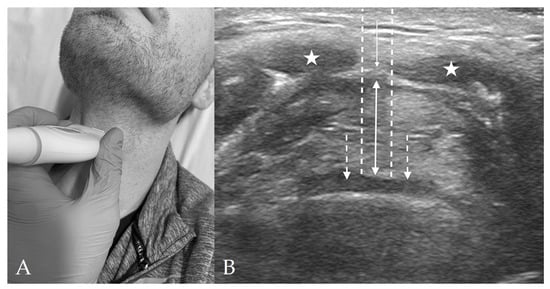

5. Sonographic Assessment of the Difficult Airway

7. Assessment of Laryngeal Edema